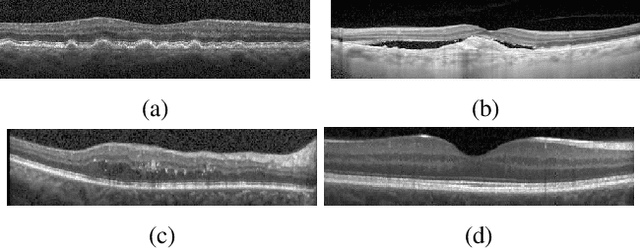

Abstract:Age-related Macular Degeneration (AMD) and Diabetic Macular Edema (DME) are the major causes of vision loss in developed countries. Alteration of retinal layer structure and appearance of exudate are the most significant signs of these diseases. With the aim of automatic classification of DME, AMD and normal subjects from Optical Coherence Tomography (OCT) images, we proposed a classification algorithm. The two important issues intended in this approach are, not utilizing retinal layer segmentation which by itself is a challenging task and attempting to identify diseases in their early stages, where the signs of diseases appear in a small fraction of B-Scans. We used a histogram of oriented gradients (HOG) feature descriptor to well characterize the distribution of local intensity gradients and edge directions. In order to capture the structure of extracted features, we employed different dictionary learning-based classifiers. Our dataset consists of 45 subjects: 15 patients with AMD, 15 patients with DME and 15 normal subjects. The proposed classifier leads to an accuracy of 95.13%, 100.00%, and 100.00% for DME, AMD, and normal OCT images, respectively, only by considering the 4% of all B-Scans of a volume which outperforms the state of the art methods.

Abstract:In recent years, there has been a growing interest in applying convolutional neural networks (CNNs) to low-level vision tasks such as denoising and super-resolution. Optical coherence tomography (OCT) images are inevitably affected by noise, due to the coherent nature of the image formation process. In this paper, we take advantage of the progress in deep learning methods and propose a new method termed multi-input fully-convolutional networks (MIFCN) for denoising of OCT images. Despite recently proposed natural image denoising CNNs, our proposed architecture allows exploiting high degrees of correlation and complementary information among neighboring OCT images through pixel by pixel fusion of multiple FCNs. We also show how the parameters of the proposed architecture can be learned by optimizing a loss function that is specifically designed to take into account consistency between the overall output and the contribution of each input image. We compare the proposed MIFCN method quantitatively and qualitatively with the state-of-the-art denoising methods on OCT images of normal and age-related macular degeneration eyes.